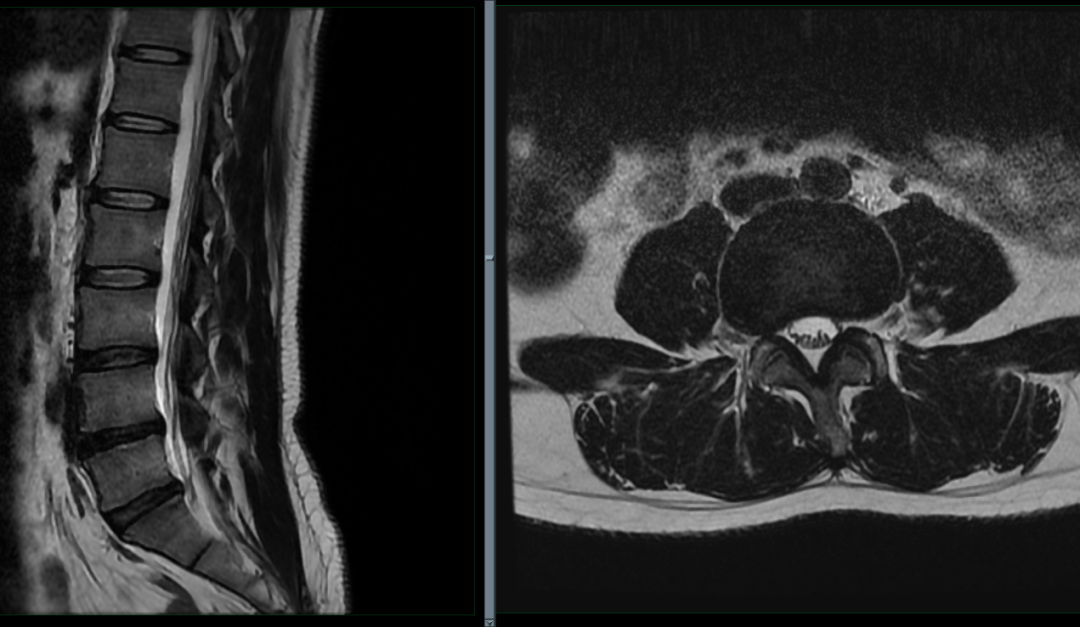

L3/4 水平:

L3/4 变性,膨出